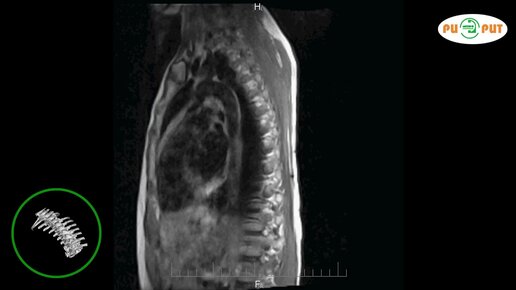

Что видно на МРТ грудного отдела позвоночника